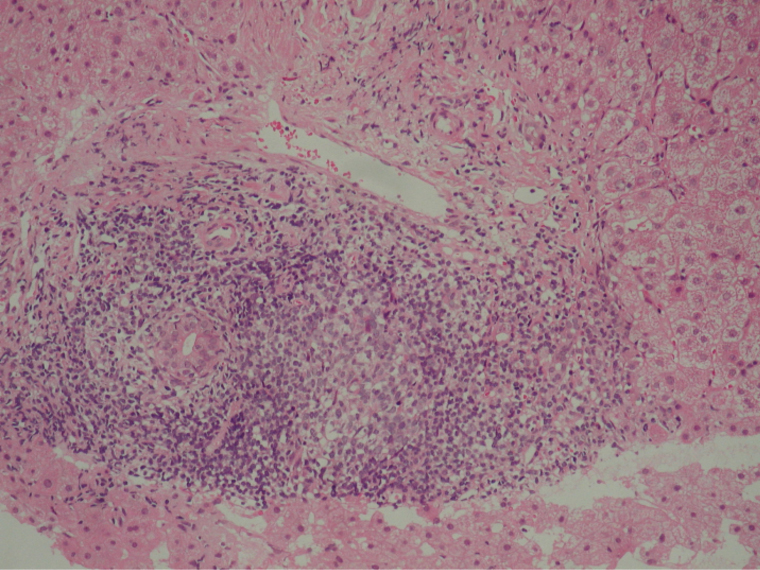

肝生検組織像(2)

線維性隔壁と門脈域に著明なリンパ球浸潤とinterface hepatitis像を認める。